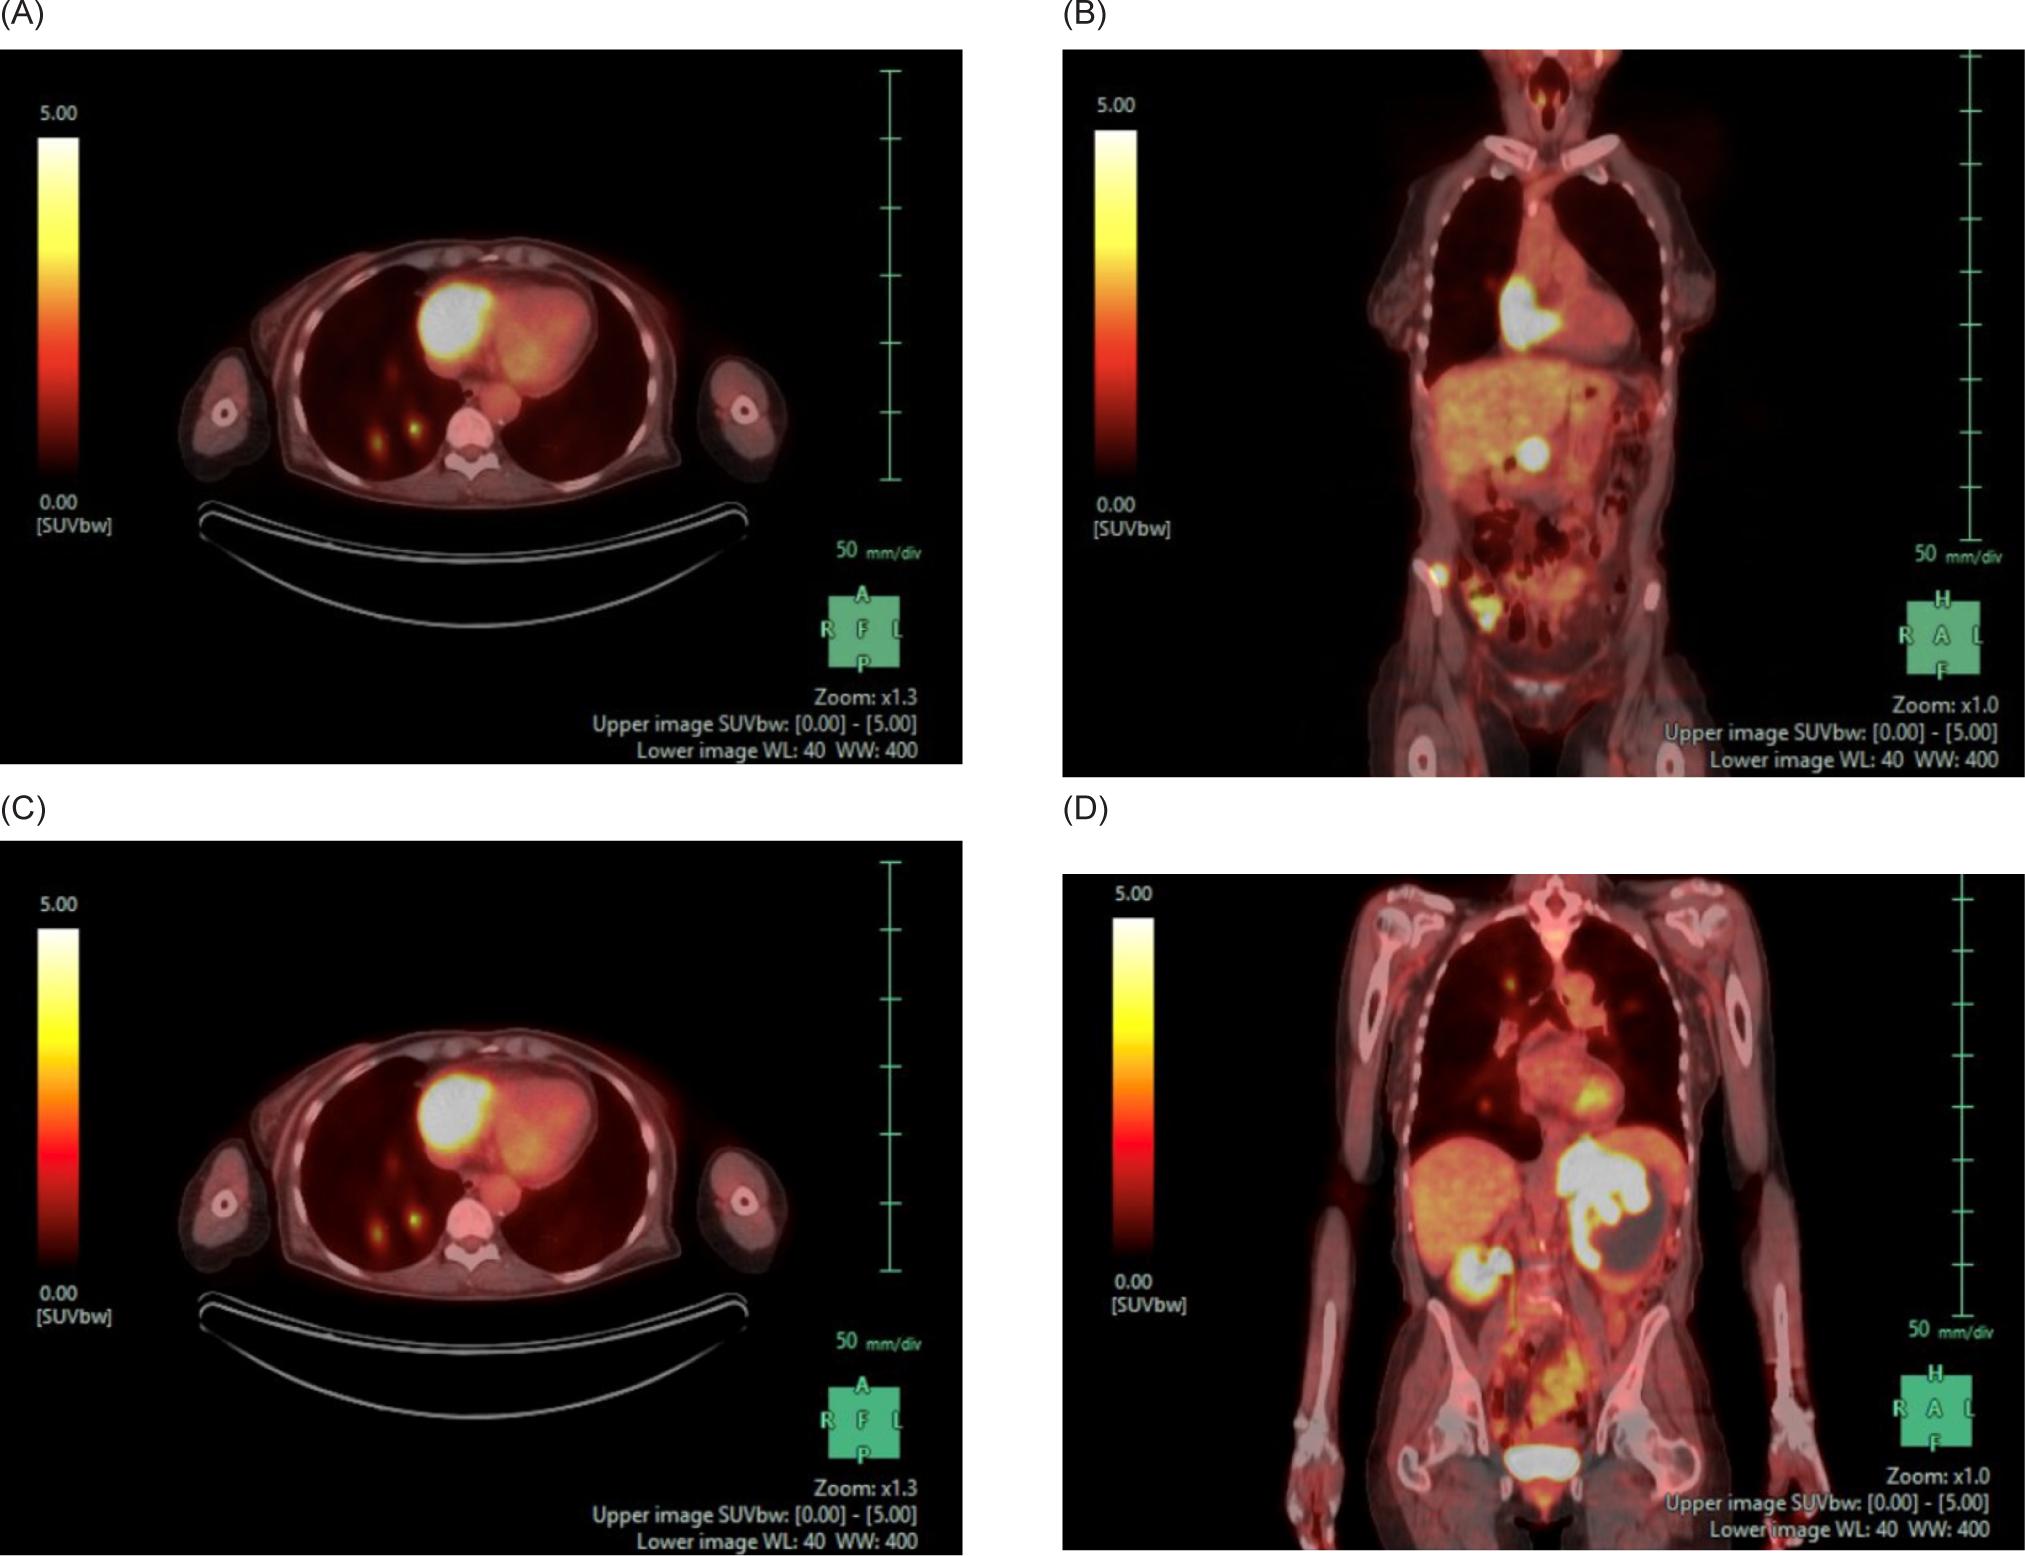

A 59-year-old female smoker with history of hypertension and hyperlipidemia who was screened for lung cancer with yearly low-dose CT scans was incidentally found to have a large left renal mass. Further evaluation via CT revealed a complex enhancing renal mass measuring 9.2.2 × 9.3 × 12.4 cm with extension into the left psoas muscle and abutting the pancreatic tail, spleen, and stomach (Figure 1). The patient underwent excision of a soft tissue mass, and surgical pathology was consistent with sarcoma. PET-CT scan revealed multiple avid lesions including lung nodules of up to 1.5 cm, a left adrenal mass, retroperitoneal adenopathy, and soft tissue metastases in the pelvic muscles as well as a lesion near the right atrium (Figure 2). An echocardiogram was performed in order to further evaluate the cardiac finding on the PET-CT scan, which revealed a 3.5 × 3.4 cm mass attached to the right atrial free wall, which was thought to represent a large thrombus or cardiac tumor, as well as a 0.75 cm mass noted on the atrial aspect of the IVC-RA junction likely representing the thrombus. Left ventricle ejection fraction was normal at 65%. The patient was instructed by her cardiologist to present to the Emergency Department for further evaluation given these findings. On presentation, the patient reported intermittent left flank pain, EKG was normal sinus rhythm with no acute ST changes, and CTA scan revealed likely invasion of perivascular nodules in the right upper lobe into subsegmental pulmonary arterial branches with associated pulmonary emboli within the distal subsegmental and more distal branches. The following day, cardiac MRI confirmed an intra-cardiac tumor occupying the entire right atrium with extension through the myocardium into the epicardial space and through the tricuspid valve into the right ventricle (Figure 3). MRI brain revealed three lesions consistent with metastatic disease. Renal biopsy was consistent with clear cell RCC with sarcomatoid features (Figure 4). Immunohistochemical studies were positive for desmin, PAX8, and myogenin, and negative for CK7. Patient was identified as poor risk per International Metastatic RCC Database Consortium (IMDC), with a median survival of 7.8 months. The patient received Ipilimumab and Nivolumab for one cycle, followed by Nivolumab only due to complication of diarrhea requiring steroid therapy. After three months of therapy that included three cycles of total therapy, she was noted to have partial response per Response Evaluation Criteria in Solid Tumors (RECIST) criteria. The patient will be continued on Nivolumab. The patient was also treated with gamma knife radiosurgery for her brain metastases.

Figure 1: CT of the abdomen and pelvis with IV contrast. (A) Transverse and (B) coronal views demonstrating a 9.2 × 9.3 × 12.4 cm left renal mass with extension into the left psoas.

Figure 2: PET-CT of the chest, abdomen, and pelvis. (A) Axial and (B) coronal views demonstrating a FDG uptake of the right atrium suggestive of a cardiac metastasis. There are also FDG avid pulmonary nodules. (C) Axial and (D) coronal views demonstrating a heterogeneously attenuating 9.6 × 8.7 cm left renal mass and accompanying 5.9 × 4.3 FDG avid adrenal mass. There is also a 2.6 × 1.2 cm FDG avid right adrenal metastasis and multiple FDG avid abdominopelvic nodules.